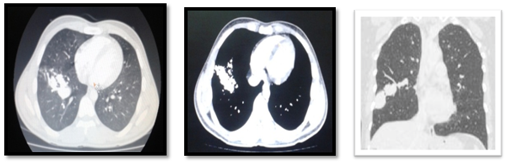

X ray chest P/A view showed a heterogeneous radio-opaque shadow in right lower zone with fluffy margins (Figure 1). CT scan showed a lobulated shadow with a feeding vessel (Figure 2a-2c). A CT Pulmonary angiogram was than performed which showed a pulmonary arterio-venous pseudoaneurism in the right lower lobe (Figure 3a-3c). Patient underwent wedge resection as the pseudoaneurism was large and coiling was not possible. Post surgery the patient has no fresh episodes of hemoptysis and is doing well.

Figure 2a-2c CT scan showed a lobulated shadow with a feeding vessel in the right lower lobe.

Figure 3a-3c CT Pulmonary angiogram showing a pulmonary arteriovenous pseudoaneurism in the right lower lobe.